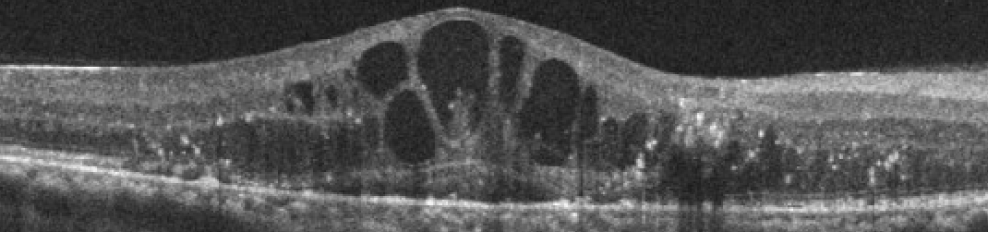

당뇨황반부종

당뇨망막병증으로 황반부종이 발생하면 중심시력이 급격하게 나빠질 수 있습니다.